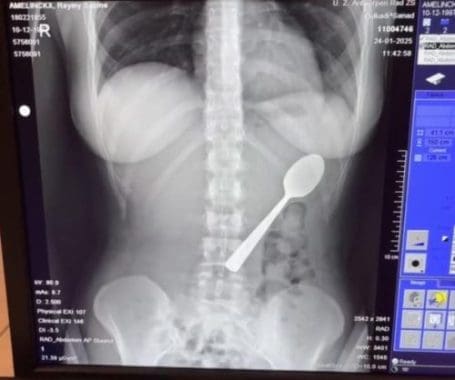

A Belgian medical representative spent two terrifying days with a 17 centimeter spoon lodged in her stomach after her dog startled her while she was eating yoghurt. Reymy Amelinckx, 28, from Rumst in northern Belgium, made the split second decision to swallow the utensil whole after it became lodged in her throat, choosing that option over the risk of choking.

Medical staff at the hospital confirmed that the spoon was too large to pass through her digestive system naturally. They scheduled a gastroscopy procedure for two days later, leaving Amelinckx to endure an uncomfortable and frightening wait at home. She described the experience as truly terrifying, stating she felt the spoon moving inside her body, sometimes even between her ribs.

The removal procedure was performed under local anaesthetic using gastroscopy, a medical technique that involves inserting a flexible tube with a camera through the mouth to examine and treat the upper digestive system. Medical staff had to carefully rotate the spoon in her stomach to extract it, which caused a small gastric haemorrhage during the process.